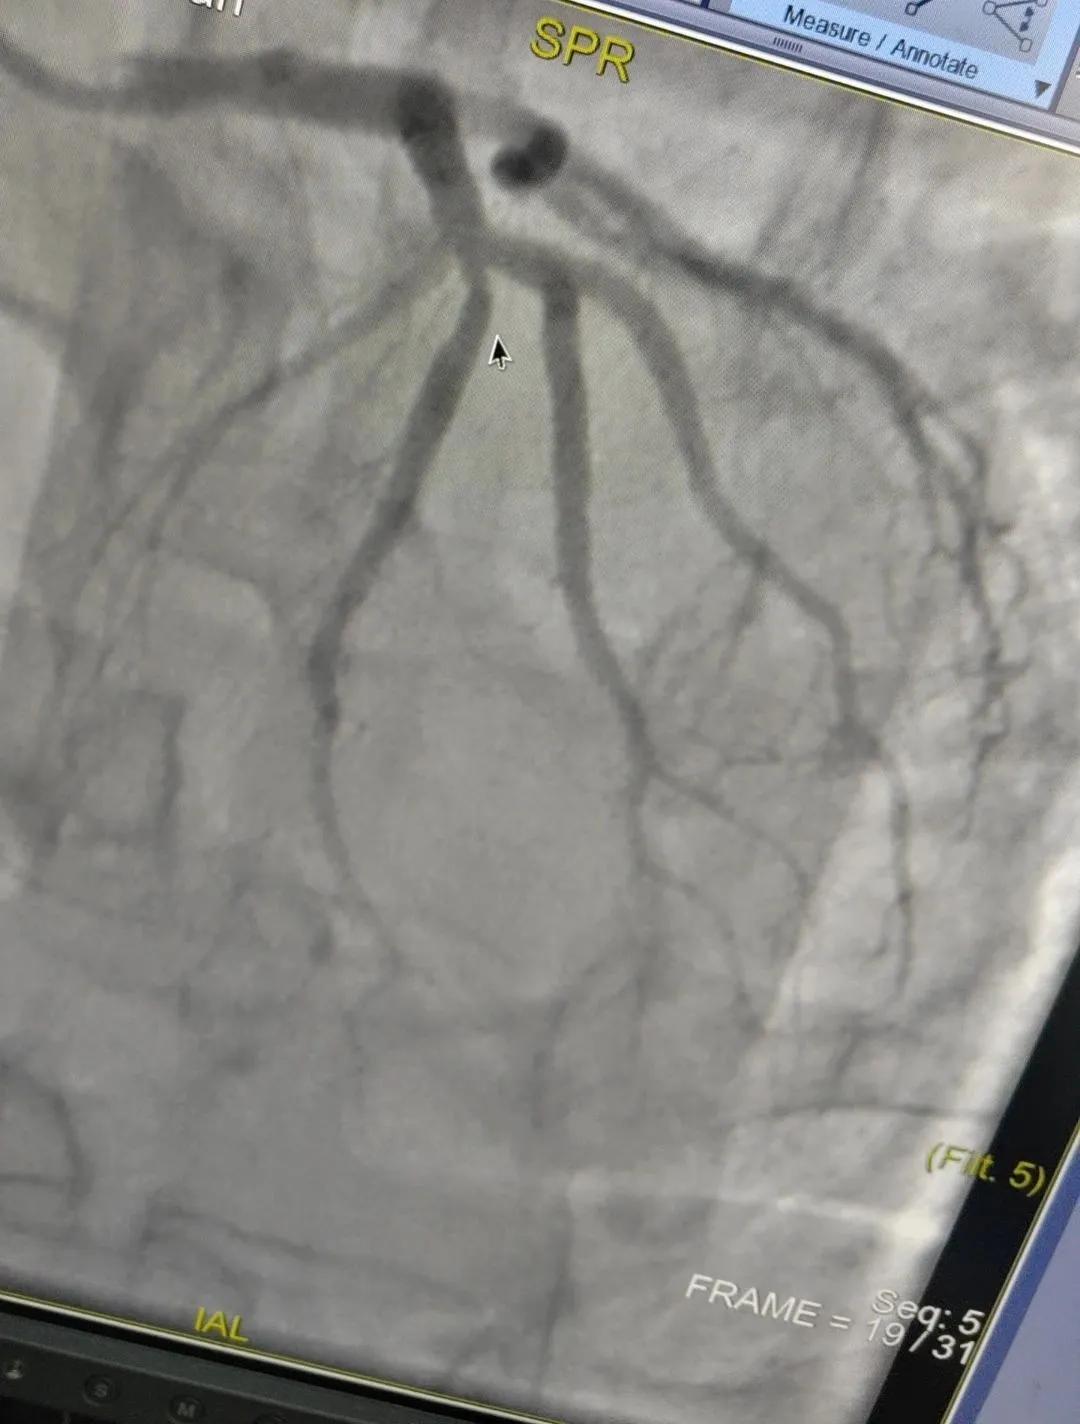

近日,漯河市中醫(yī)院成功開展了一例心腦血管聯(lián)合造影的手術(shù)。

患者男,37歲,兩周前無明顯誘因突發(fā)頭昏,伴右側(cè)肢體無力來院就診,經(jīng)過對(duì)患者病情的評(píng)估以及心內(nèi)科和腦病科醫(yī)生聯(lián)合會(huì)診,需對(duì)患者進(jìn)行心腦血管聯(lián)合造影手術(shù)。由神經(jīng)內(nèi)科楊慶堂副主任與心血管內(nèi)科陳云副主任帶領(lǐng)各自的介入團(tuán)隊(duì)為該患者順利進(jìn)行了全腦血管造影術(shù)+心血管造影的介入檢查。

術(shù)中心血管造影顯示:LAD中段發(fā)出D1處可見約50%節(jié)段性狹窄,RCA中段狹窄約40%,PLA可見約70%狹窄病變。

心腦聯(lián)合造影不僅明確患者的病因和病變血管,還為下一步治療提供了有力的依據(jù)。

心腦聯(lián)合造影的優(yōu)勢(shì):一次穿刺就可以同時(shí)完成腦和心臟的血管檢查,避免二次穿刺,且經(jīng)橈動(dòng)脈入路的全腦血管造影,相比較傳統(tǒng)股動(dòng)脈造影而言,對(duì)穿刺部位損傷更小,并發(fā)癥更少,術(shù)后易于壓迫止血。